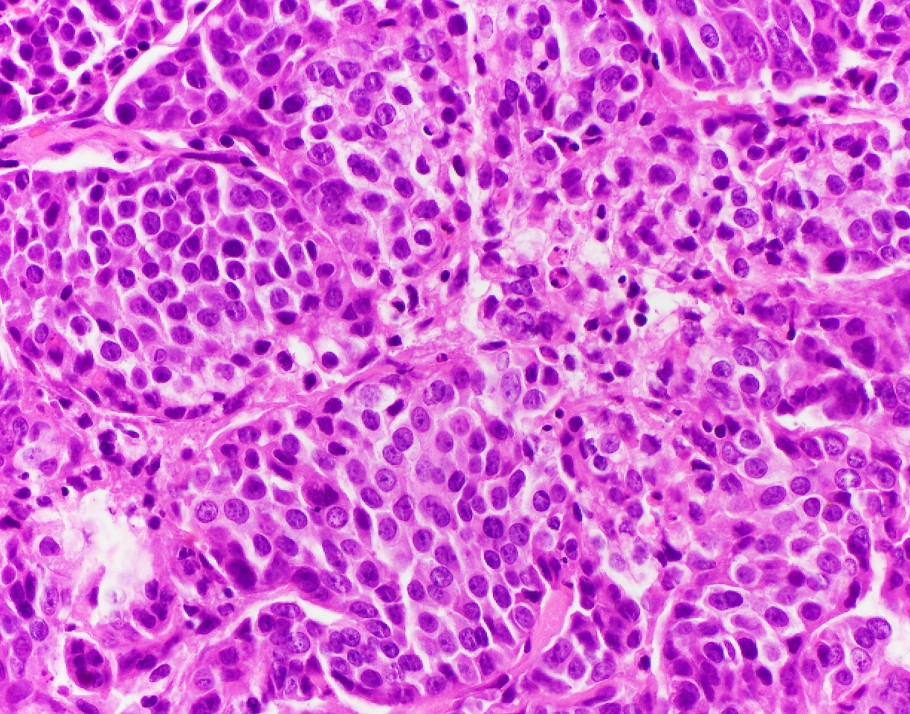

Explanation: INI-1 (SMARCB1)-deficient sinonasal carcinoma, currently listed as a subtype of sinonasal undifferentiated carcinoma (SNUC) in the current WHO Classification of Head and Neck Tumors, is a poorly differentiated sinonasal carcinoma defined by loss of nuclear INI-1 expression due to SMARCB1 deletion (1). Histologically, they have a definitive (adeno)carcinoma appearance unlike other INI-1-deficient tumors such as epithelioid sarcoma and atypical teratoid/rhabdoid tumor. INI-1-deficient sinonasal carcinoma shows islands of eosinophilic/oncocytoid and plasmacytoid carcinoma cells with variable glandular differentiation to include focal intracellular/intraluminal mucin production, and may also show a basaloid appearance (2). INI-1 (SMARCB1)-deficient sinonasal carcinoma typically shows expression of CK7. In one report 3 of 10 showed p40 expression, 4 of 12 examples showed CDX2 expression, and 3 of 12 showed CK20 expression (3). Variable/weak expression of neuroendocrine markers has been described. INI-1 (SMARCB1)-deficient sinonasal carcinoma is negative for high-risk HPV and EBV and is negative for S100 protein expression.

The differential diagnosis of INI-1 (SMARCB1)-deficient sinonasal carcinoma includes high-grade non-intestinal sinonasal adenocarcinoma, myoepithelial carcinoma, nonkeratinizing squamous cell carcinoma, mucosal melanoma, etc. All of the entities in the differential diagnosis, except a proportion of myoepithelial carcinomas, retain INI-1 expression. Myoepithelial carcinoma, unlike INI-1 (SMARCB1)-deficient sinonasal carcinoma, should express S100 protein and other myoepithelial markers (3). Recently the morphologic spectrum of INI-1 (SMARCB1)-deficient sinonasal carcinomas has been expanded to included examples with yolk-sac-like areas that have also shown limited glypican-3, SALL4, and HepPar-1 expression, adding germ cell tumor and metastatic hepatocellular carcinoma to the differential diagnosis (3).